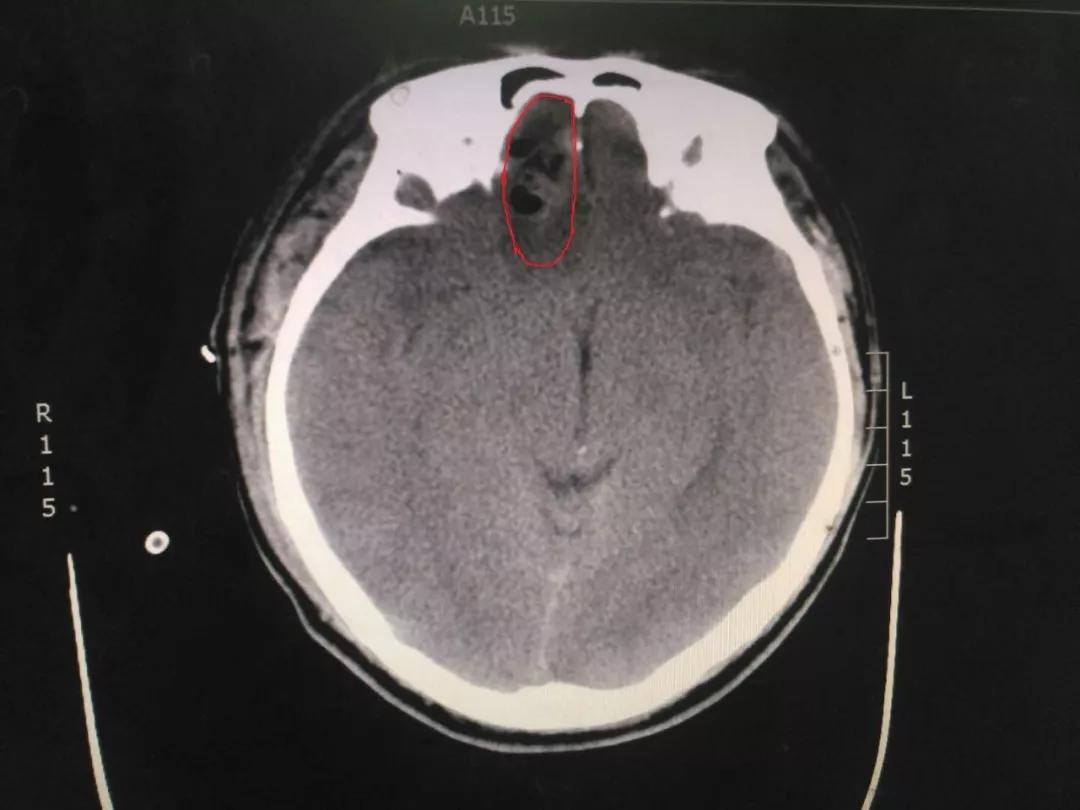

近日,我神经外科收治了一位29岁因意外头颅严重外伤患者。患者亲友叙述,患者在摔倒后头痛剧烈、意识不清。王占尧主任医师立即安排为该患者查体,各个检查科室也为患者开通绿色通道,大家一起为这个29岁的年轻人鼓劲加油。

初步诊察发现患者右侧瞳孔散大,CT结果显示右侧额叶脑挫裂伤,部分血肿位于前颅凹底,位置深,清除困难,这给治疗带来了一定的难度。王占尧主任医师随即决定应用神经内镜辅助清除血肿,并采用右侧额颞弧形切口,避免采取传统的双额冠状切口,骨窗大小仅有4cmX4cm,大大减少了手术创伤,也相应减少了住院手术的费用,减轻了患者负担。术后第二天,患者意识恢复,复查CT显示血肿清除效果满意。